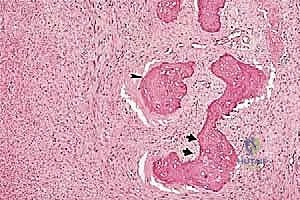

تتميز هذه الأورام بقدرتها على اختراق الأنسجة المجاورة وتكوين ما يُعرف بـ "المنطقة التفاعلية" (Reactive Zone) أو الكبسولة الكاذبة، والتي تحتوي غالباً على خلايا سرطانية مجهرية. هذا المفهوم البيولوجي هو ما يوجه الدكتور محمد هطيف في تحديد مدى الاستئصال الجراحي.

1. درجة الورم (Grade - G): بناءً على الفحص النسيجي (G1 منخفض الدرجة، G2 عالي الدرجة).

يتم تقييم مدى استجابة الورم للعلاج الكيميائي (Tumor Necrosis Rate) بعد الاستئصال، وهو مؤشر قوي لفرص الشفاء التام.